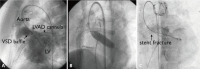

Figures